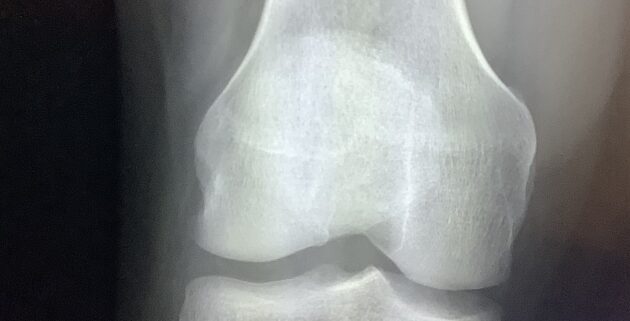

Correlating clinically involves several key components, which include analysis of various diagnostic modalities. Radiological examinations such as X-rays, MRI, and CT scans generate critical images that reveal structural abnormalities. However, these images alone are often insufficient. They must be interpreted in the context of the patient’s physical manifestations and clinical history, such as symptoms, prior medical conditions, and family history. Thus, a comprehensive evaluate of the patient’s situation is critical in establishing an accurate diagnosis.